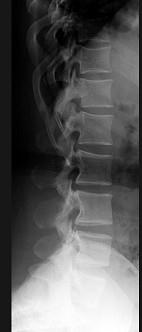

女,41岁,身材矮小,背痛,请结合图像,选出最可能的诊断 ( )A、石骨症B、马方综合征C、腰椎间盘突出D、软骨发育不全E、腰椎退行性变

问题 女,41岁,身材矮小,背痛,请结合图像,选出最可能的诊断 ( )

选项 A、石骨症 B、马方综合征 C、腰椎间盘突出 D、软骨发育不全 E、腰椎退行性变

答案 D